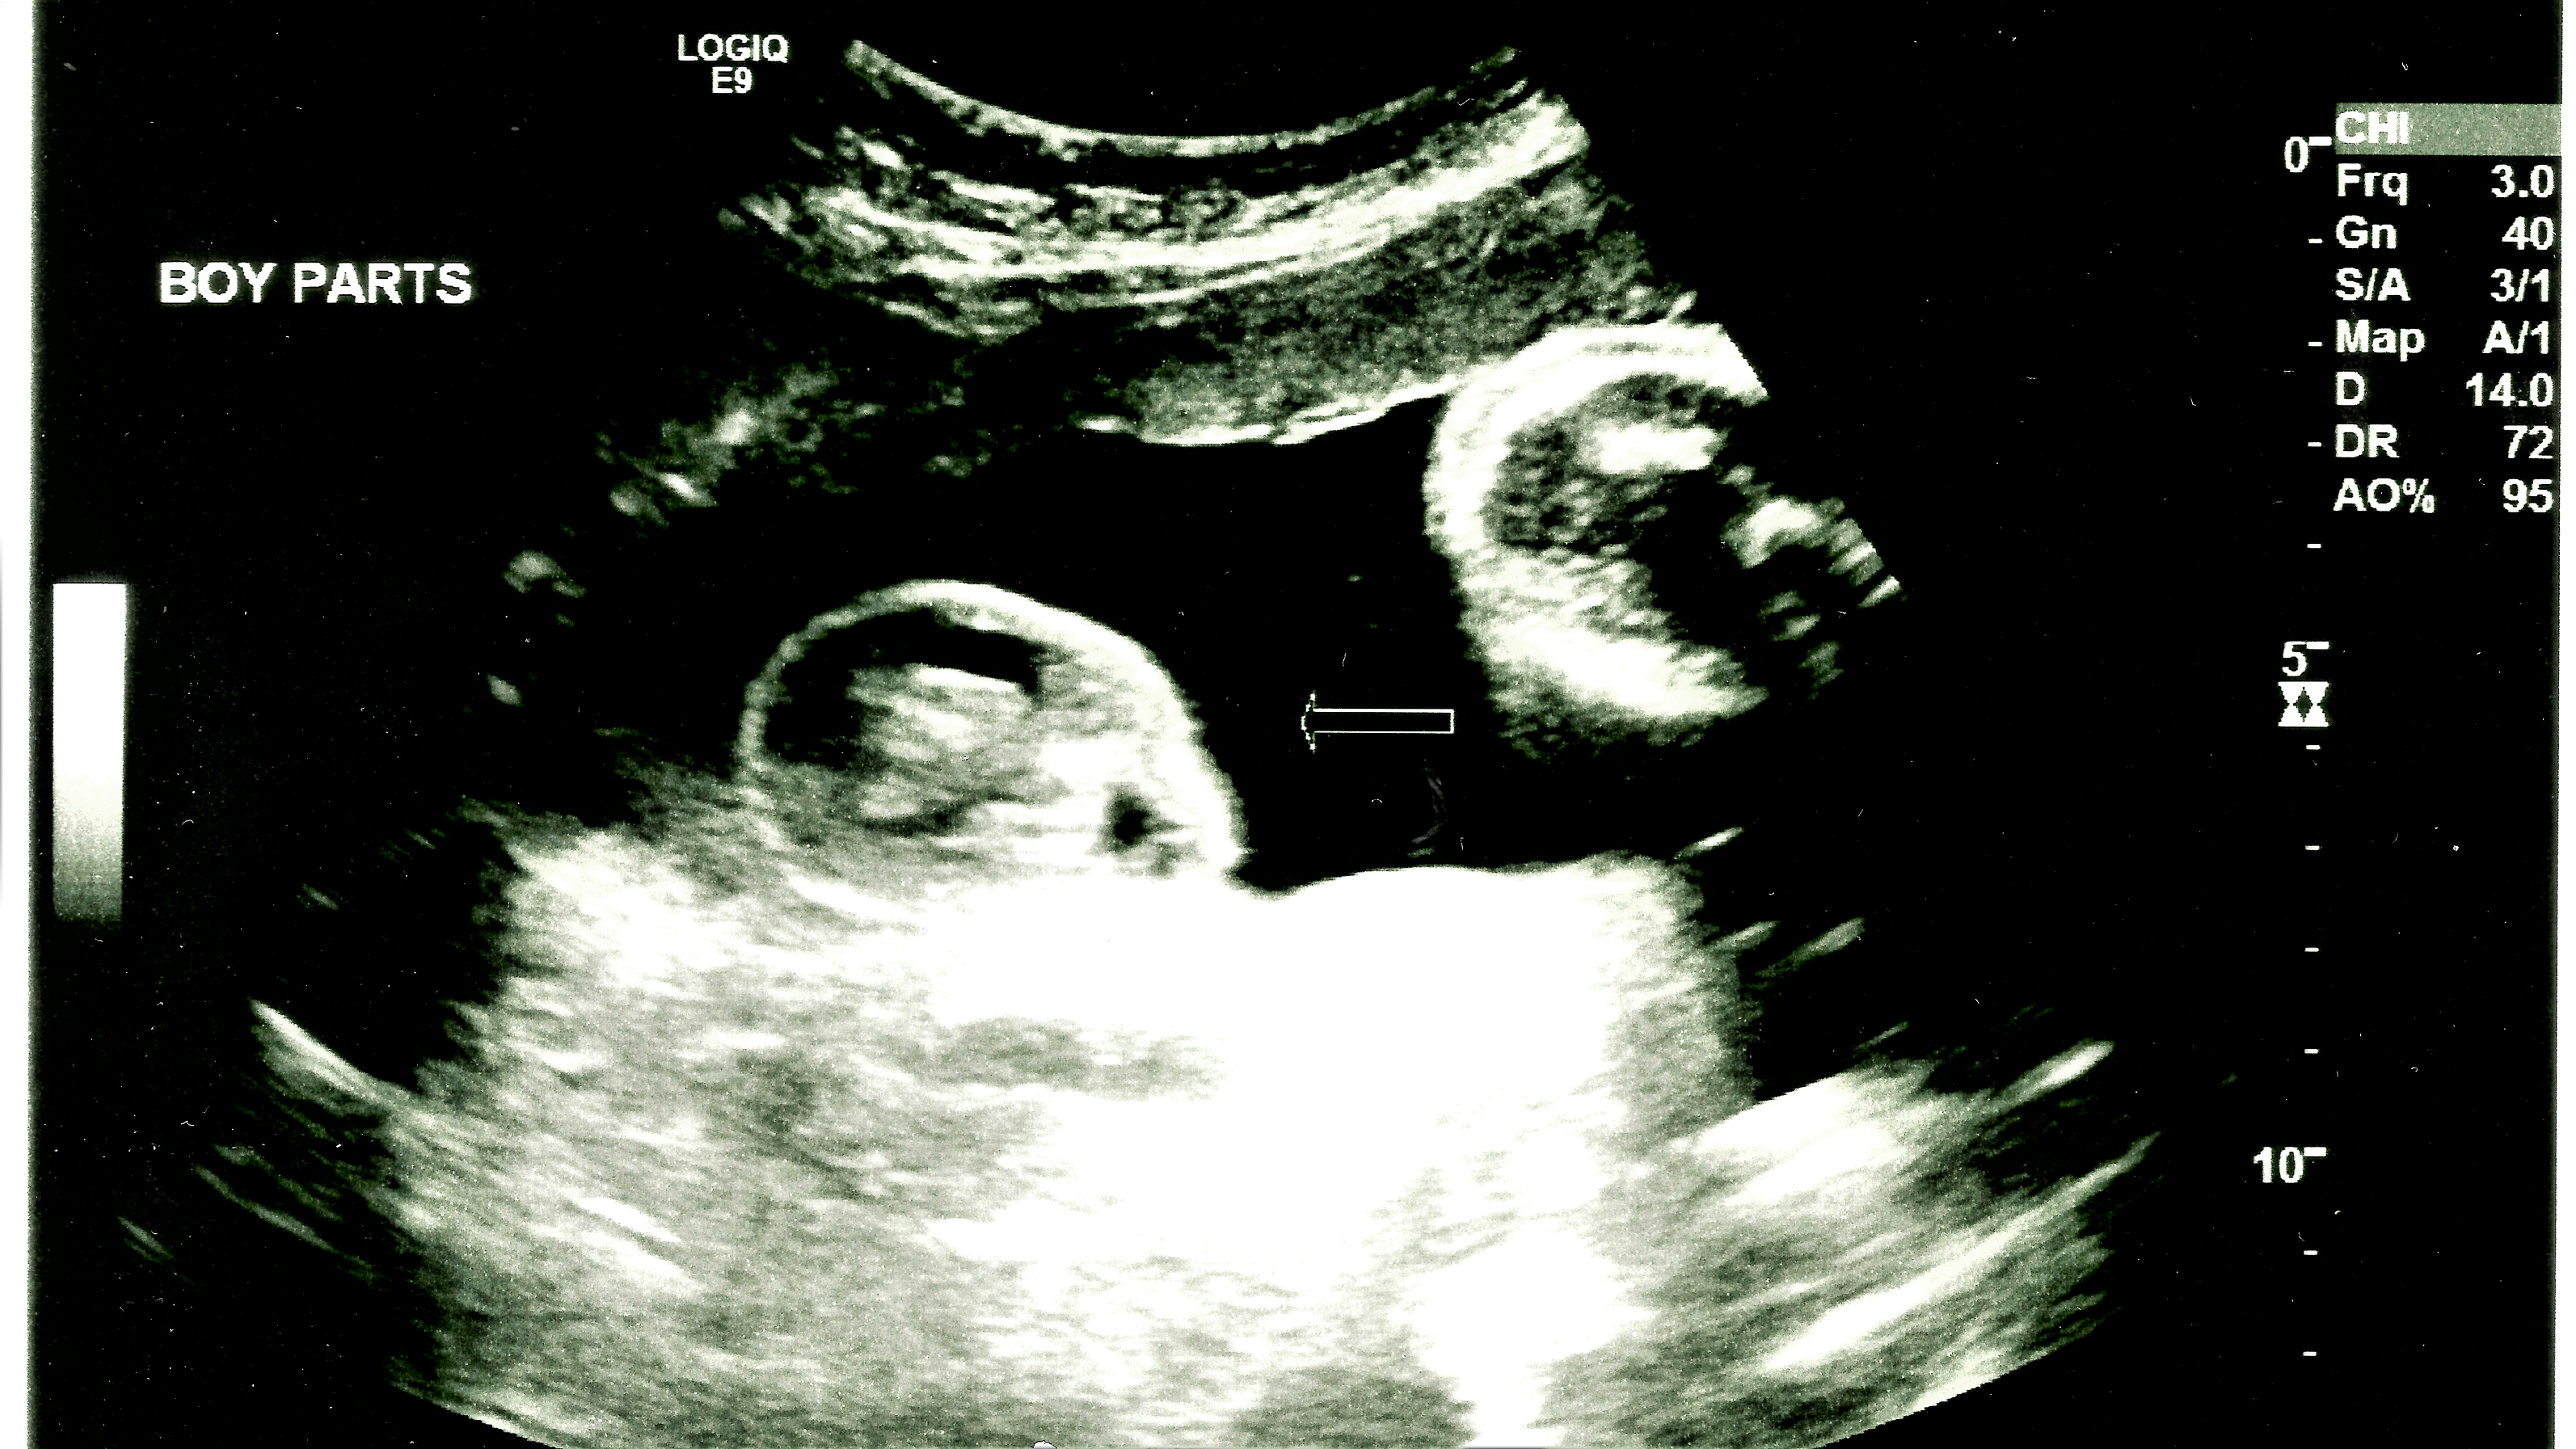

My wife recently had an ultrasound.

We’re due to have another baby soon, but my wife’s measurements gave the doctor cause for concern. So we had an anatomy ultrasound to make sure everything was okay. And of course, everything is okay.

I guess you don’t usually get this ultrasound so late in pregnancy (unless your insurance is awesome I guess), but the baby is larger than expected and they wanted to check. That’s good.

What’s amazing was being able to see his little features through the monitor.

His nose. His lips. His eyes. His puff cheeks.

I was definitely feeling emotional. This little guy is ready and now we wait.